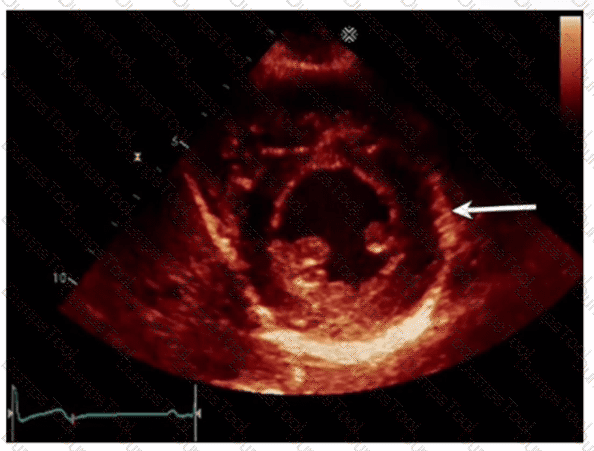

Which congenital abnormality is most consistent with the findings in this video?